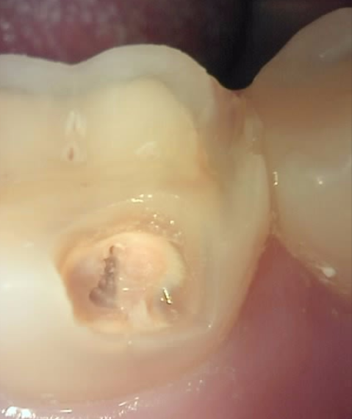

Before

육안으로는 잘 식별하기 어려운 치아 우식을

큐레이로 촬영해보면 붉은색으로 쉽게 발견할 수 있습니다.

치아 우식균 내부에 있는 포르피린 단백질을 검출하여 형광 분홍색으로 보여줌으로써

잔존 우식을 남기지 않고 제거할 수 있게 도와줍니다.